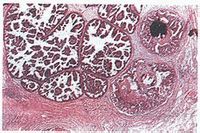

原位癌上皮組織是覆蓋身體表面及體內臟器的內、外表面的一層組織,包括若干層上皮細胞和基底膜。其下是間質和真皮組織。原位癌就是指癌細胞只出現在上皮層內。而未破壞基底膜,或侵入其下的間質或真皮組織。更沒有發生浸潤和遠處轉移,所以原位癌有時也被稱為“浸潤前癌”或“0期癌”。

原位癌可進一步發展為早期浸潤癌,偶爾原位癌可消退。原位癌的病變範圍雖為局限性,但也可程多灶性或在不穿透基底膜的情況下累及較大的區域。